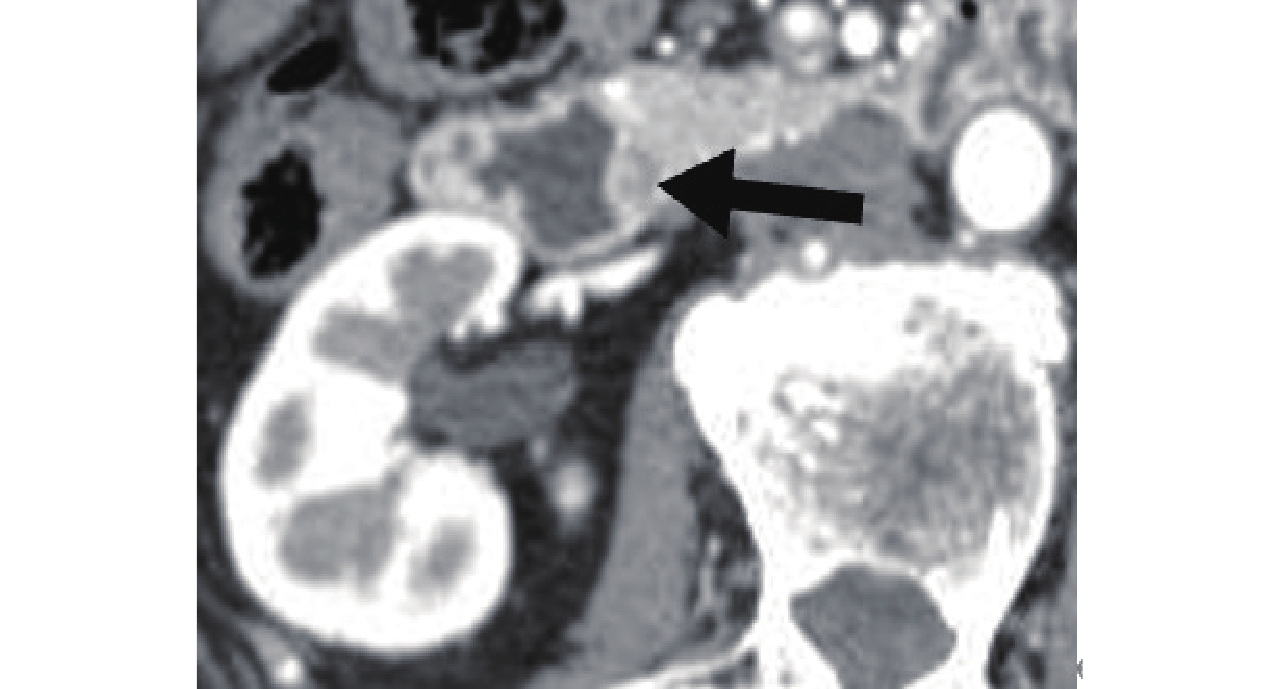

![]() 图 4 CPR显示十二指肠乳头癌表现为十二指肠乳头增大呈葫芦状(倒“3”字形)(白箭头),胆总管(粗黑箭头)、胰管(细黑箭头)扩张并截断于肿瘤Figure 4. CPR, duodenal papillary carcinoma, gourd-shaped (Inverted "3") and enlarged duodenal papilla with enlarged common bile duct (thick black arrow) and pancreatic duct (thin black arrow) which got cut off at duodenal papilla tumor

图 4 CPR显示十二指肠乳头癌表现为十二指肠乳头增大呈葫芦状(倒“3”字形)(白箭头),胆总管(粗黑箭头)、胰管(细黑箭头)扩张并截断于肿瘤Figure 4. CPR, duodenal papillary carcinoma, gourd-shaped (Inverted "3") and enlarged duodenal papilla with enlarged common bile duct (thick black arrow) and pancreatic duct (thin black arrow) which got cut off at duodenal papilla tumor3. 讨论

图 4 CPR显示十二指肠乳头癌表现为十二指肠乳头增大呈葫芦状(倒“3”字形)(白箭头),胆总管(粗黑箭头)、胰管(细黑箭头)扩张并截断于肿瘤

Figure 4. CPR, duodenal papillary carcinoma, gourd-shaped (Inverted "3") and enlarged duodenal papilla with enlarged common bile duct (thick black arrow) and pancreatic duct (thin black arrow) which got cut off at duodenal papilla tumor